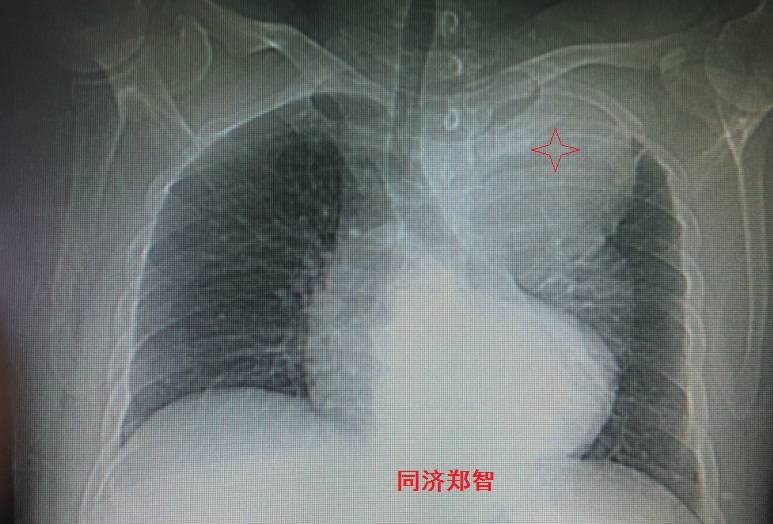

病例一

胸片提示左上纵隔影增宽(红色星形标记),CTA证实B型主动脉夹层伴降主动脉夹层动脉瘤形成。